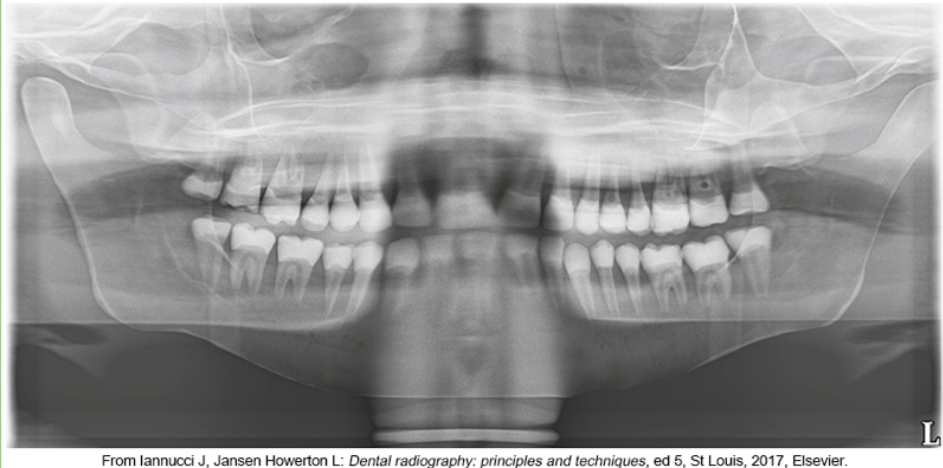

whats the problem

chin too high